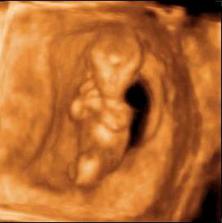

Tak jsme se dočkali!Dne 15.10.2007 nám bylo potvrzeno ultrazvukem těhotenství (5.týden)Na miminko se strašně moc těšíme a doufáme ,že vše bude probíhat tak jak má 🙂.Bereme vitamíny Gravital,osvědčily se nám i u Tomáška 🙂.Za 14 dní jdeme na ultrazvuk,tak se moc těším.Věciček máme hodně,ale samozřejmě budeme nakupovat o to víc pokud to bude holčička ,kterou bychom si mooooc přáli,ale hlavní je abychom byli zdraví 🙂.Dnes tj.28.11.jsem byla na 3D ultrazvuku (12.týden),tak jsem sem přidala nějake foto 🙂.Tak dnes 30.1.2008 jsem byla opět na 3D ultrazvuku (21.týden) a zjistili jsme ,že čekáme holčičku.Tak se nám povedl páreček.S manželem máme velkou radost,protože jsme si holčičku moc přáli 🙂).Tak ve 32.týdnu potvrzena holčička.Zatím vyhrává jméno Valérie.Ve 32.týdnu važíme cca 1924g 🙂).Tomíček se na sestřičku moooooc těší a už teď mi se vším pomáhá.